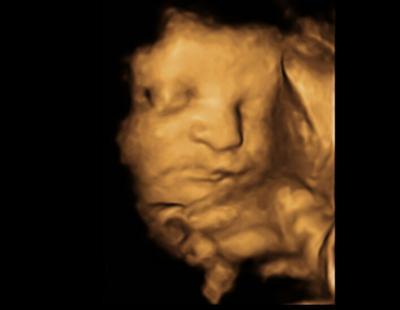

Gerade beim Arzt raus. Unser Bauchzwerg wiegt ca. 1700g und ist ca.42cm groß. CTG war ok. Blutdruck super. Urin sind leukos drin. Hab was bekommen zum einmaligen trinken für die blase. Muss am 05.06. zur Schwangerenintensivberatung in die Landesfrauenklinik. Da wird auch unter anderem der Kaiserschnitt besprochen. Bin ab morgen 31.Ssw aber laut Ultraschall schon 32.Woche

Bild zu 3.Screening - Forum für August - Mamis

Wow ist ja schon eine ordentliche größe! Tolles Bild. Freut mich, dass alles gut ist!!